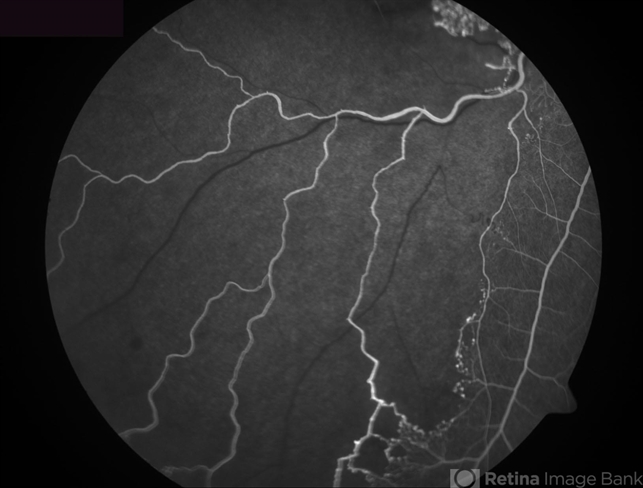

- Ischemic Branch Retinal Vein Occlusion

- branch retinal vein occlusion (BRVO), capillary nonperfusion

- Fluorescein angiogram inferior to the macular area, showing wide areas of capillary nonperfusion.